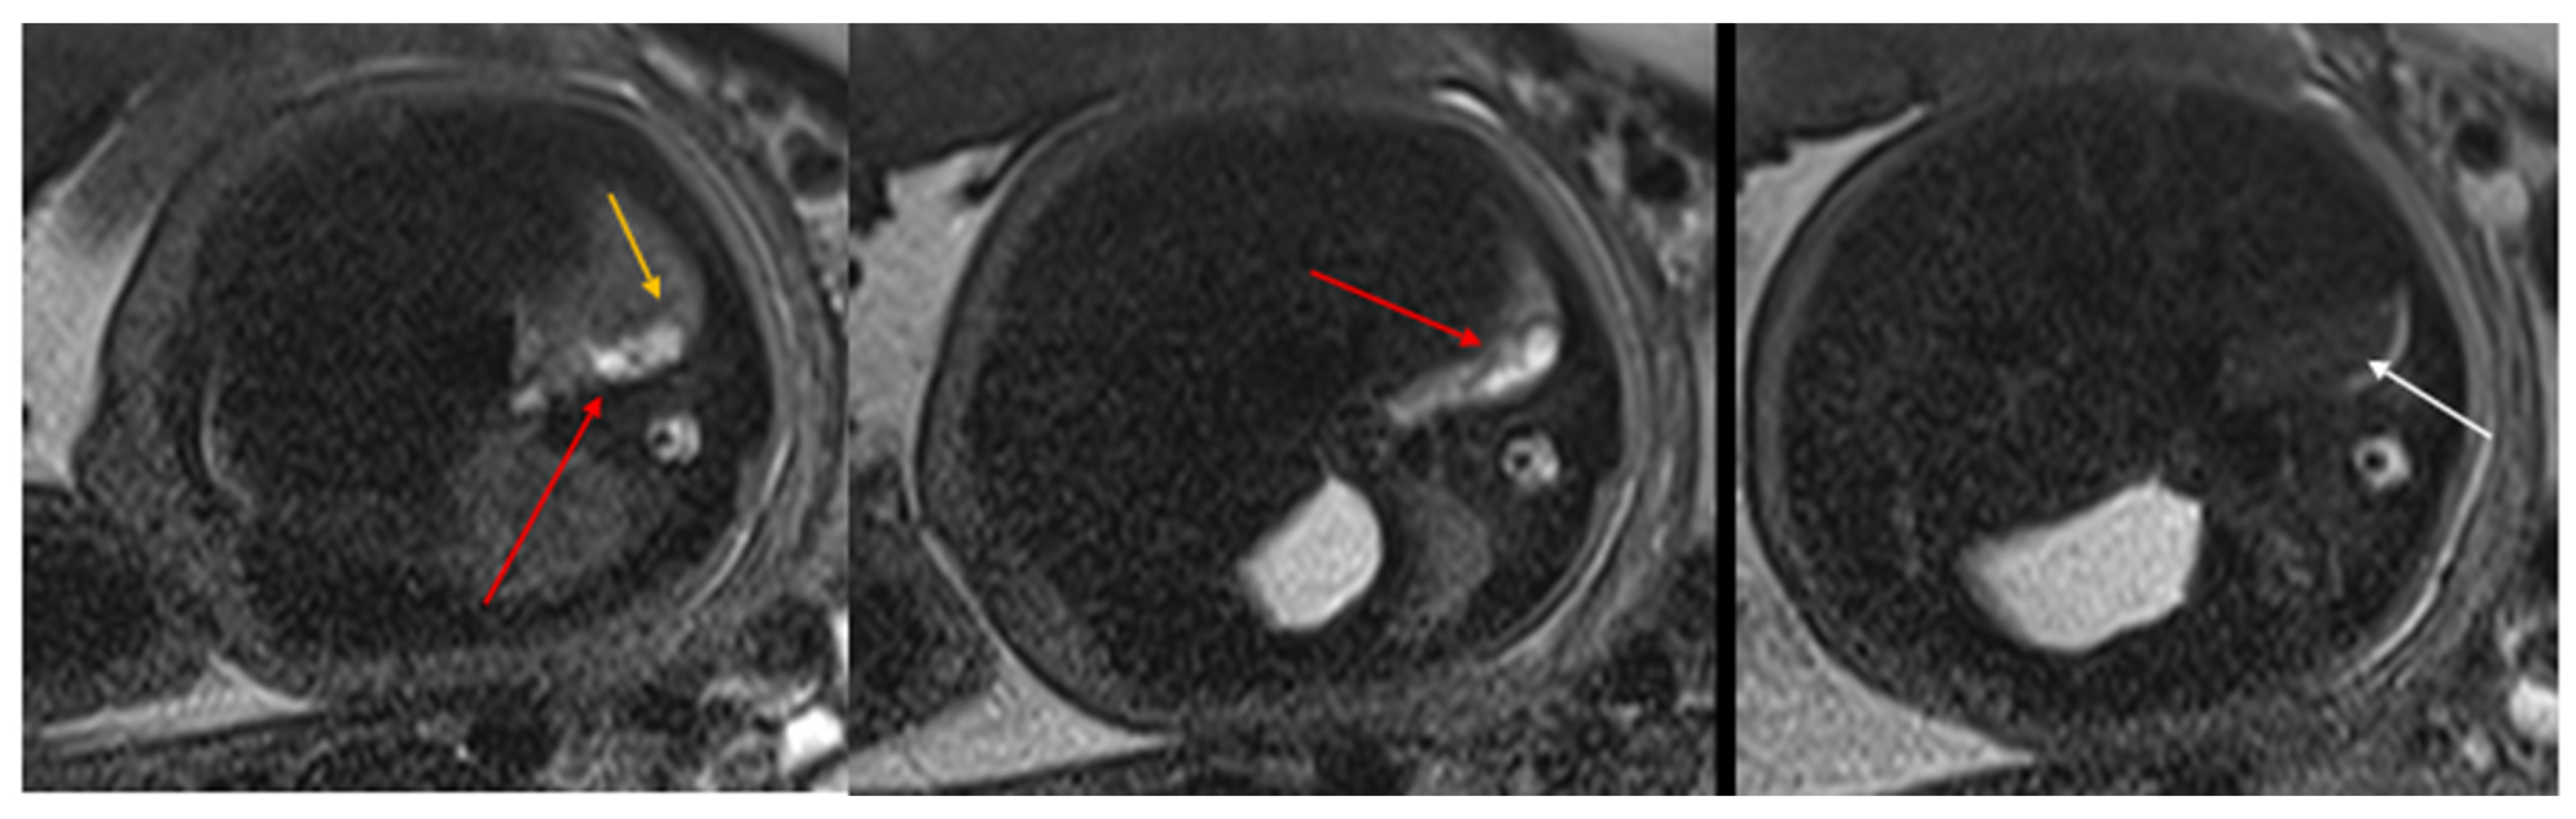

Figure 3. CPAM type III. Coronal T2 HASTE image shows, diffuse hyperintensity of the entire left lung (white arrow), without evidence of recognizable cystic structures. Note the normal intensity of the right lung (red arrow).

Figure 4. Sagittal T1w FLASH MRI sequence shows increased signal intensity in the left abnormal pulmonary parenchyma (white arrow) and the compressed signal of the right lung (red arrow). A differential diagnosis to consider is congenital lobar overinflation (CLO), where a more homogeneous signal intensity would typically be observed.